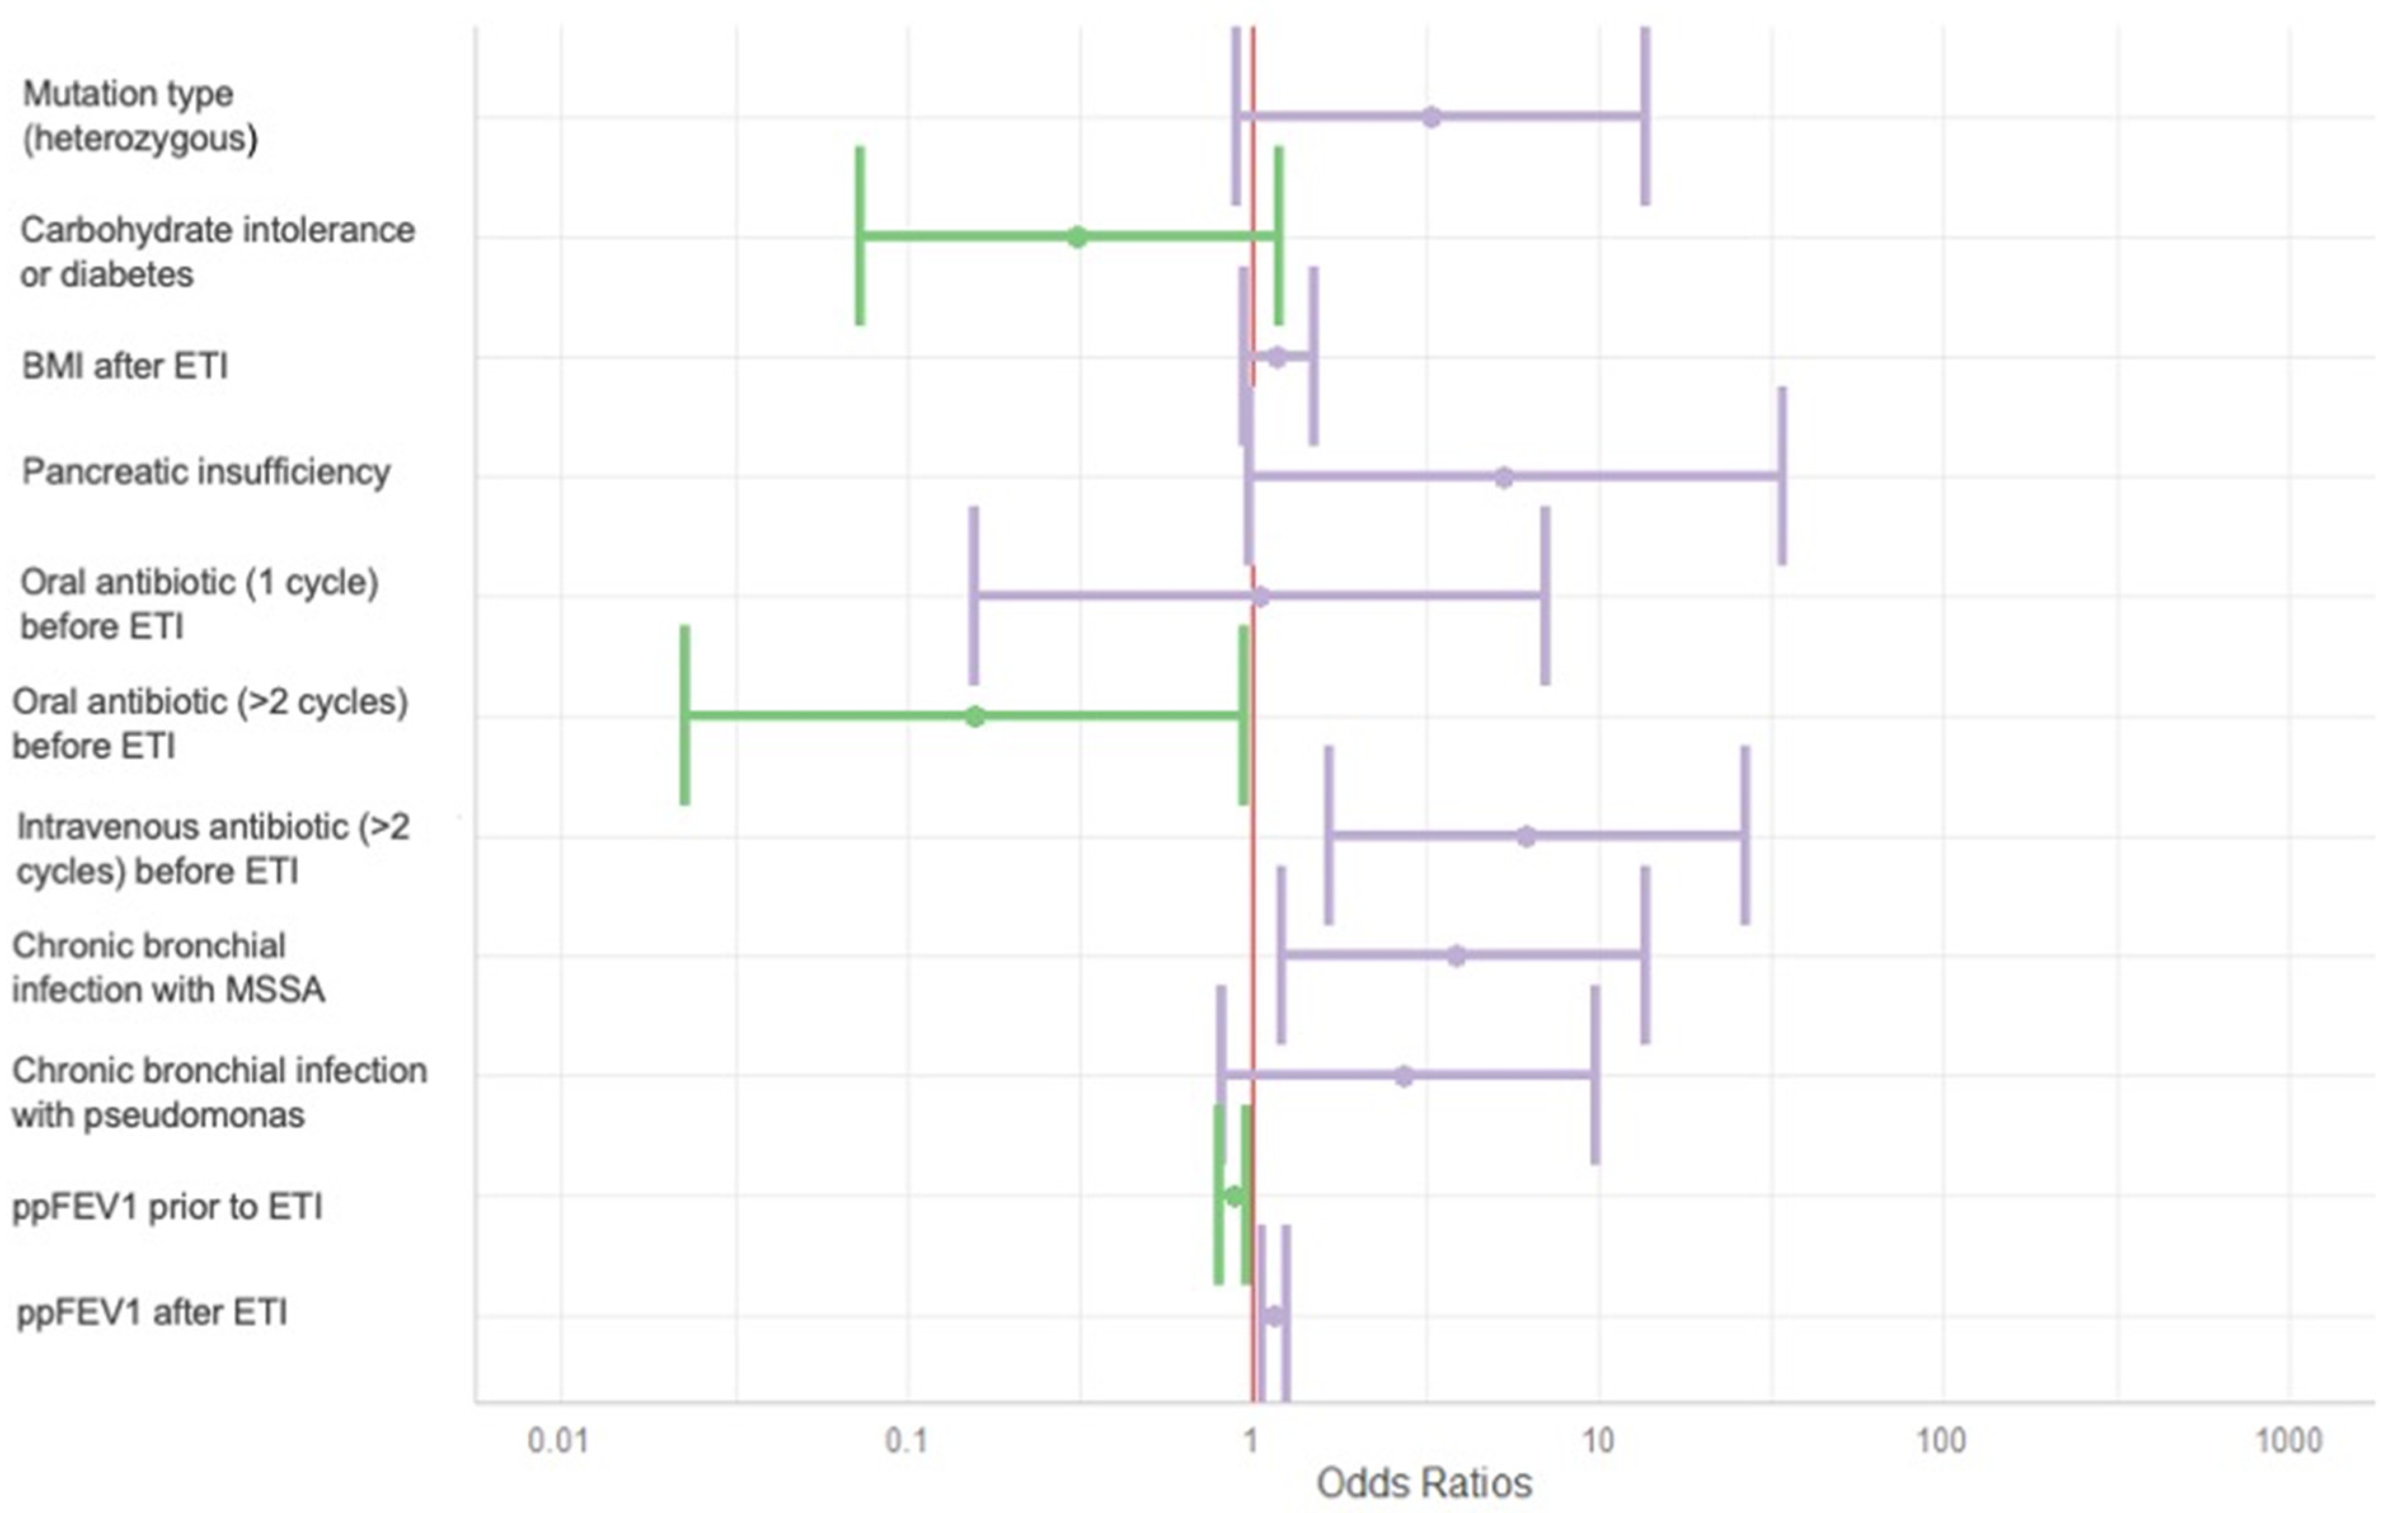

3.5. Factors Influencing the Evolution of the Bhalla Score

In the multivariate analysis (Table 5 and Figure 4), the following variables were independently associated with improvement in the Bhalla score after at least one year of ETI therapy: having received more than two courses of intravenous antibiotics in the year prior to ETI initiation (OR 6.2 [1.7–26.9]); chronic bronchial infection with methicillin-sensitive Staphylococcus aureus (MSSA) (OR 3.9 [1.2–13.7], p = 0.027); and higher ppFEV1, following ETI treatment (OR 1.1 [1.1–1.3], p = 0.002).

Figure 4.

Forest plot of Bhalla score evolution predictors. BMI: body mass index. ETI: elexacaftor–tezacaftor–ivacaftor. MSSA: methicillin-sensitive Staphilococcus aureus. ppFEV1: percentage of predicted forced expiratory volume in the first second. Variables associated with a decline in the Bhalla score are shown in green, while those associated with an improvement are shown in purple.

Conversely, more than two courses of oral antibiotics in the year prior to ETI (OR 0.2 [0.0–0.9], p = 0.047), and lower ppFEV1 before ETI initiation (OR 0.9 [0.8–1.0], p = 0.005) were inversely associated with changes in the Bhalla score.

Other variables assessed, including mutation type, pancreatic insufficiency, and BMI, were not associated with changes in the Bhalla score over time.